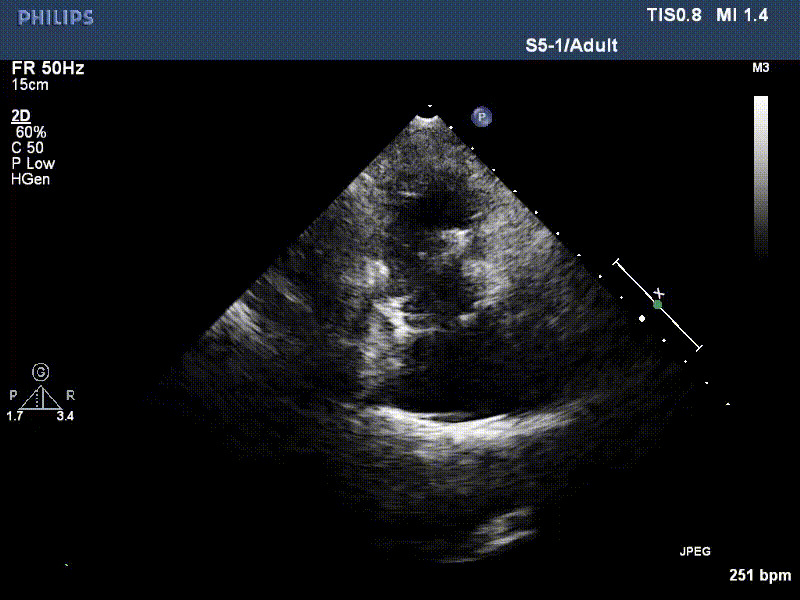

流并分別伴有房顫和房撲,高外科手術(shù)風(fēng)險。術(shù)前超聲提示,兩例患者下腔靜脈寬度分別為13mm和29mm,右房內(nèi)徑(上下徑和左右徑)分別為52×41mm和53×43mm,彩色多普勒顯示極重度三尖瓣反流,VCW分別為14×15mm和10mm。

1年前,兩例患者因難治性雙下肢水腫輾轉(zhuǎn)多家醫(yī)院尋求救治,考慮到兩例患者高齡、基礎(chǔ)疾病多、STS評分高,不適合傳統(tǒng)外科開胸手術(shù),葛均波院士及其團(tuán)隊周達(dá)新教授、潘文志教授、張源博士、陳莎莎博士、陳丹丹博士聯(lián)合心外科王春生、魏來主任,麻醉科繆長虹、郭克芳主任以及心超室的潘翠珍教授、李偉教授共同討論決定,采用我國創(chuàng)新器械LuX-Valve Plus經(jīng)血管三尖瓣置換系統(tǒng)為患者進(jìn)行手術(shù)。相較于第一代產(chǎn)品LuX-Valve,LuX-Valve Plus經(jīng)血管三尖瓣置換系統(tǒng)對輸送系統(tǒng)進(jìn)行了全面升級,實現(xiàn)了經(jīng)頸靜脈入路的方式,進(jìn)一步減小了手術(shù)風(fēng)險和對患者的創(chuàng)傷。目前隨訪1年心超結(jié)果顯示,三尖瓣極重度反流消失,人工三尖瓣瓣膜穩(wěn)定牢固,瓣葉活動度良好,右心室及下腔靜脈明顯縮小,心輸出量增加。兩位老人手術(shù)后沒有出現(xiàn)過胸悶氣促的癥狀,下肢水腫緩解,活動耐力提升,生活質(zhì)量也大為提高。

圖2 患者植入LuX-Valve Plus后,1年隨訪心超提示無三尖瓣反流